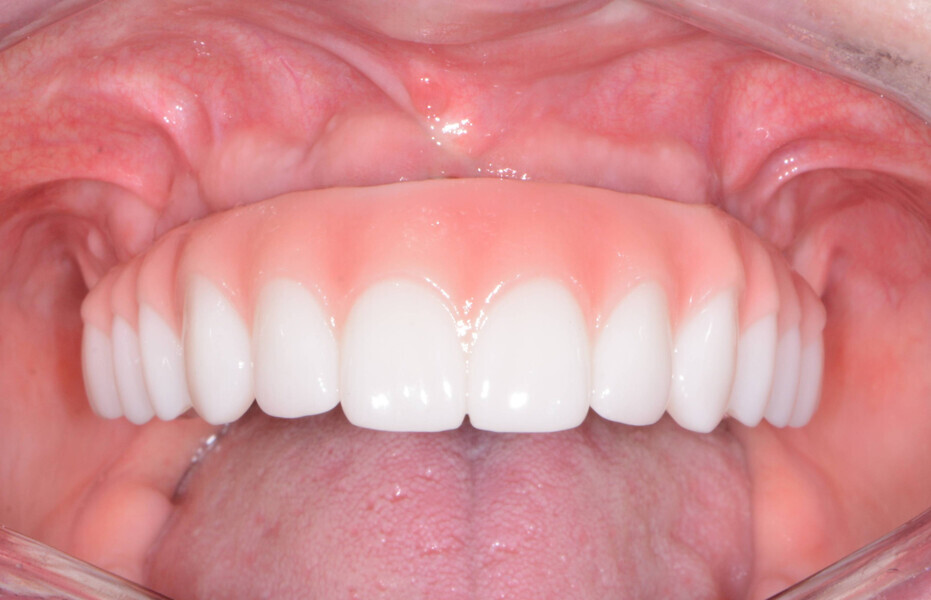

Once tried in, the restoration was evaluated for midline, incisal edge and smile line. The occlusal record was accomplished using Futar Fast bite registration material (Kettenbach). Within several weeks, the definitive restoration (monolithic zirconia on a titanium frame) was completed and delivered to the dental practice (Figs. 15 & 16). When the patient returned, the hybrid restoration was inserted and torqued to the manufacturer’s suggested settings (Figs. 17–19) and the access openings were sealed with PTFE, followed by composite.

The patient was instructed on how to clean and maintain her dental restoration. In addition, we reviewed the importance of scheduled professional cleaning and overall oral health habits. With her enhanced look, the patient was motivated to care for her investment (Fig. 20).